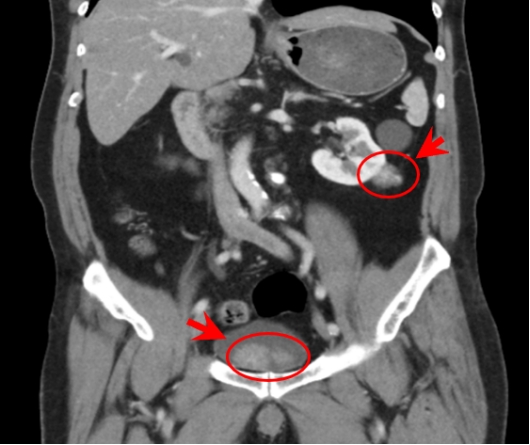

泌尿外科徐桂彬主任接诊后,进一步检查发现膀胱有个125px的大肿瘤,肾也有个50px的肿瘤,膀胱肿瘤病理检查恶性程度较低,考虑如果切除整个膀胱对王伯的生活影响较大。在经过充分评估后,徐桂彬主任团队决定保留膀胱,且同时将肾脏和膀胱肿瘤一次手术切除。

▲ (注:图片由供稿科室提供)